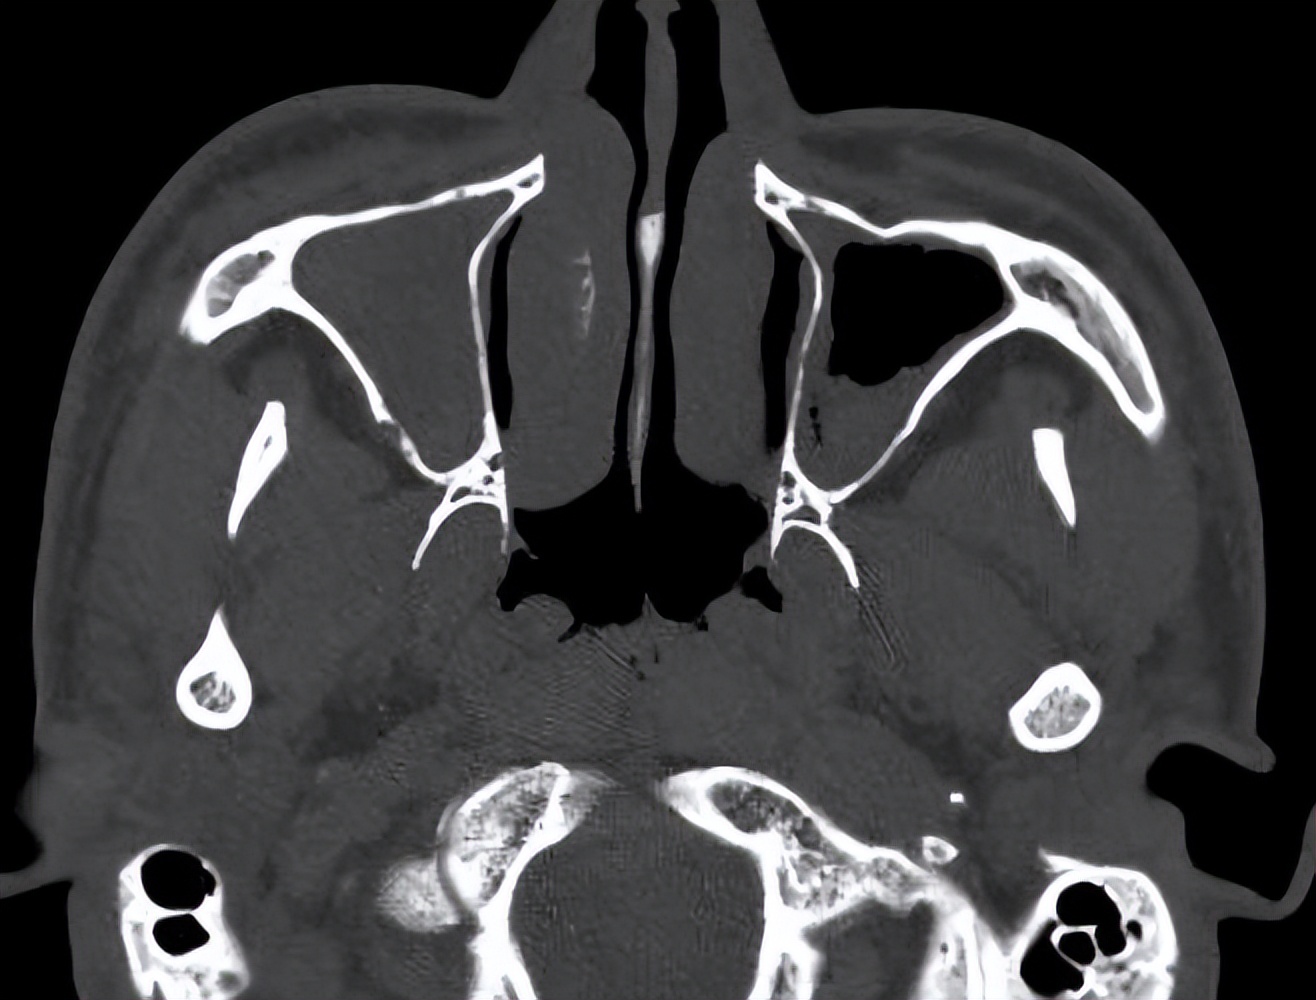

但容易反复,这次有时间找到耳鼻喉郑立岗医生,检查后考虑是过敏性鼻炎为主,由于长期的控制不佳,导致伴发了鼻窦炎和鼻息肉,这种情况一般建议手术治疗效果会更好一些。

和家人商量后决定做手术治疗,就入院了。这次安排的是鼻内镜鼻窦炎微创手术和下鼻甲手术,插管全麻后就开始了手术。在鼻内镜下切除鼻息肉和开放鼻窦后,清除了炎症病变,并做了鼻甲的射频治疗,解决鼻炎的问题,整个的手术非常的顺利,用时约一个多小时。术后查房患者无明显的不适,无手术相关的并发症。